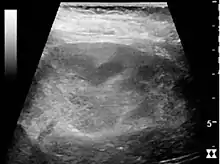

In medical imaging, the acute changes in the kidney are often examined with renal ultrasonography as the first-line modality, where CT scan and magnetic resonance imaging (MRI) are used for the follow-up examinations and when US fails to demonstrate abnormalities. In evaluation of the acute changes in the kidney, the echogenicity of the renal structures, the delineation of the kidney, the renal vascularity, kidney size and focal abnormalities are observed.[16] CT is preferred in renal traumas, but US is used for follow-up, especially in the patients suspected for the formation of urinomas. A CT scan of the abdomen will also demonstrate bladder distension or hydronephrosis.

Renal ultrasonograph of acute pyelonephritis with increased cortical echogenicity and blurred delineation of the upper pole.[16]

Renal ultrasonograph of acute pyelonephritis with increased cortical echogenicity and blurred delineation of the upper pole.[16] Renal ultrasonograph in renal failure after surgery with increased cortical echogenicity and kidney size. Biopsy showed acute tubular necrosis.[16]

Renal ultrasonograph in renal failure after surgery with increased cortical echogenicity and kidney size. Biopsy showed acute tubular necrosis.[16] Renal ultrasonograph in renal trauma with laceration of the lower pole and subcapsular fluid collection below the kidney.[16]

Renal ultrasonograph in renal trauma with laceration of the lower pole and subcapsular fluid collection below the kidney.[16]